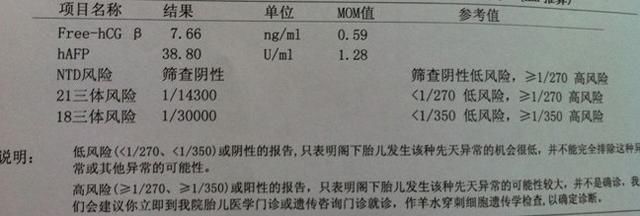

2.唐氏筛查

唐氏筛查顾名思义就是在产前对唐氏综合症胎儿检查筛选,查胎儿21三体综合症的重要指标。若筛查结果为高危需要进行进一步确诊性检查——羊膜穿刺检查。孕早期进行的唐筛检查的时间为11~14周,最佳时间为11~12周。孕中期唐氏筛查的时间为怀孕15~20周期间,最佳检查时间是在16~18周之间。